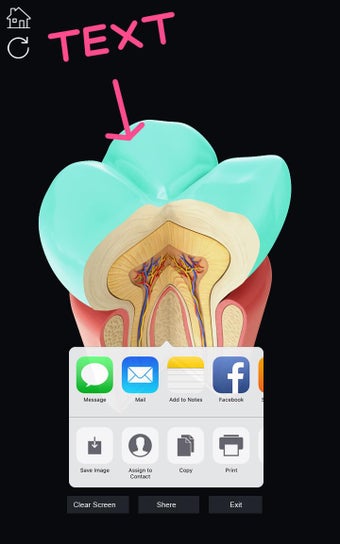

Uygulama, her bir parçayı seçerek adını görüntülemenize veya ilgili bilgileri okumanıza olanak tanır. Her bir parçayı gizlemeyi veya göstermeyi seçebilirsiniz. Ayrıca 360° döndürebilir veya yakınlaştırıp uzaklaştırabilirsiniz. Kamerayı modelin farklı bir görünümünü elde etmek için hareket ettirebilirsiniz.